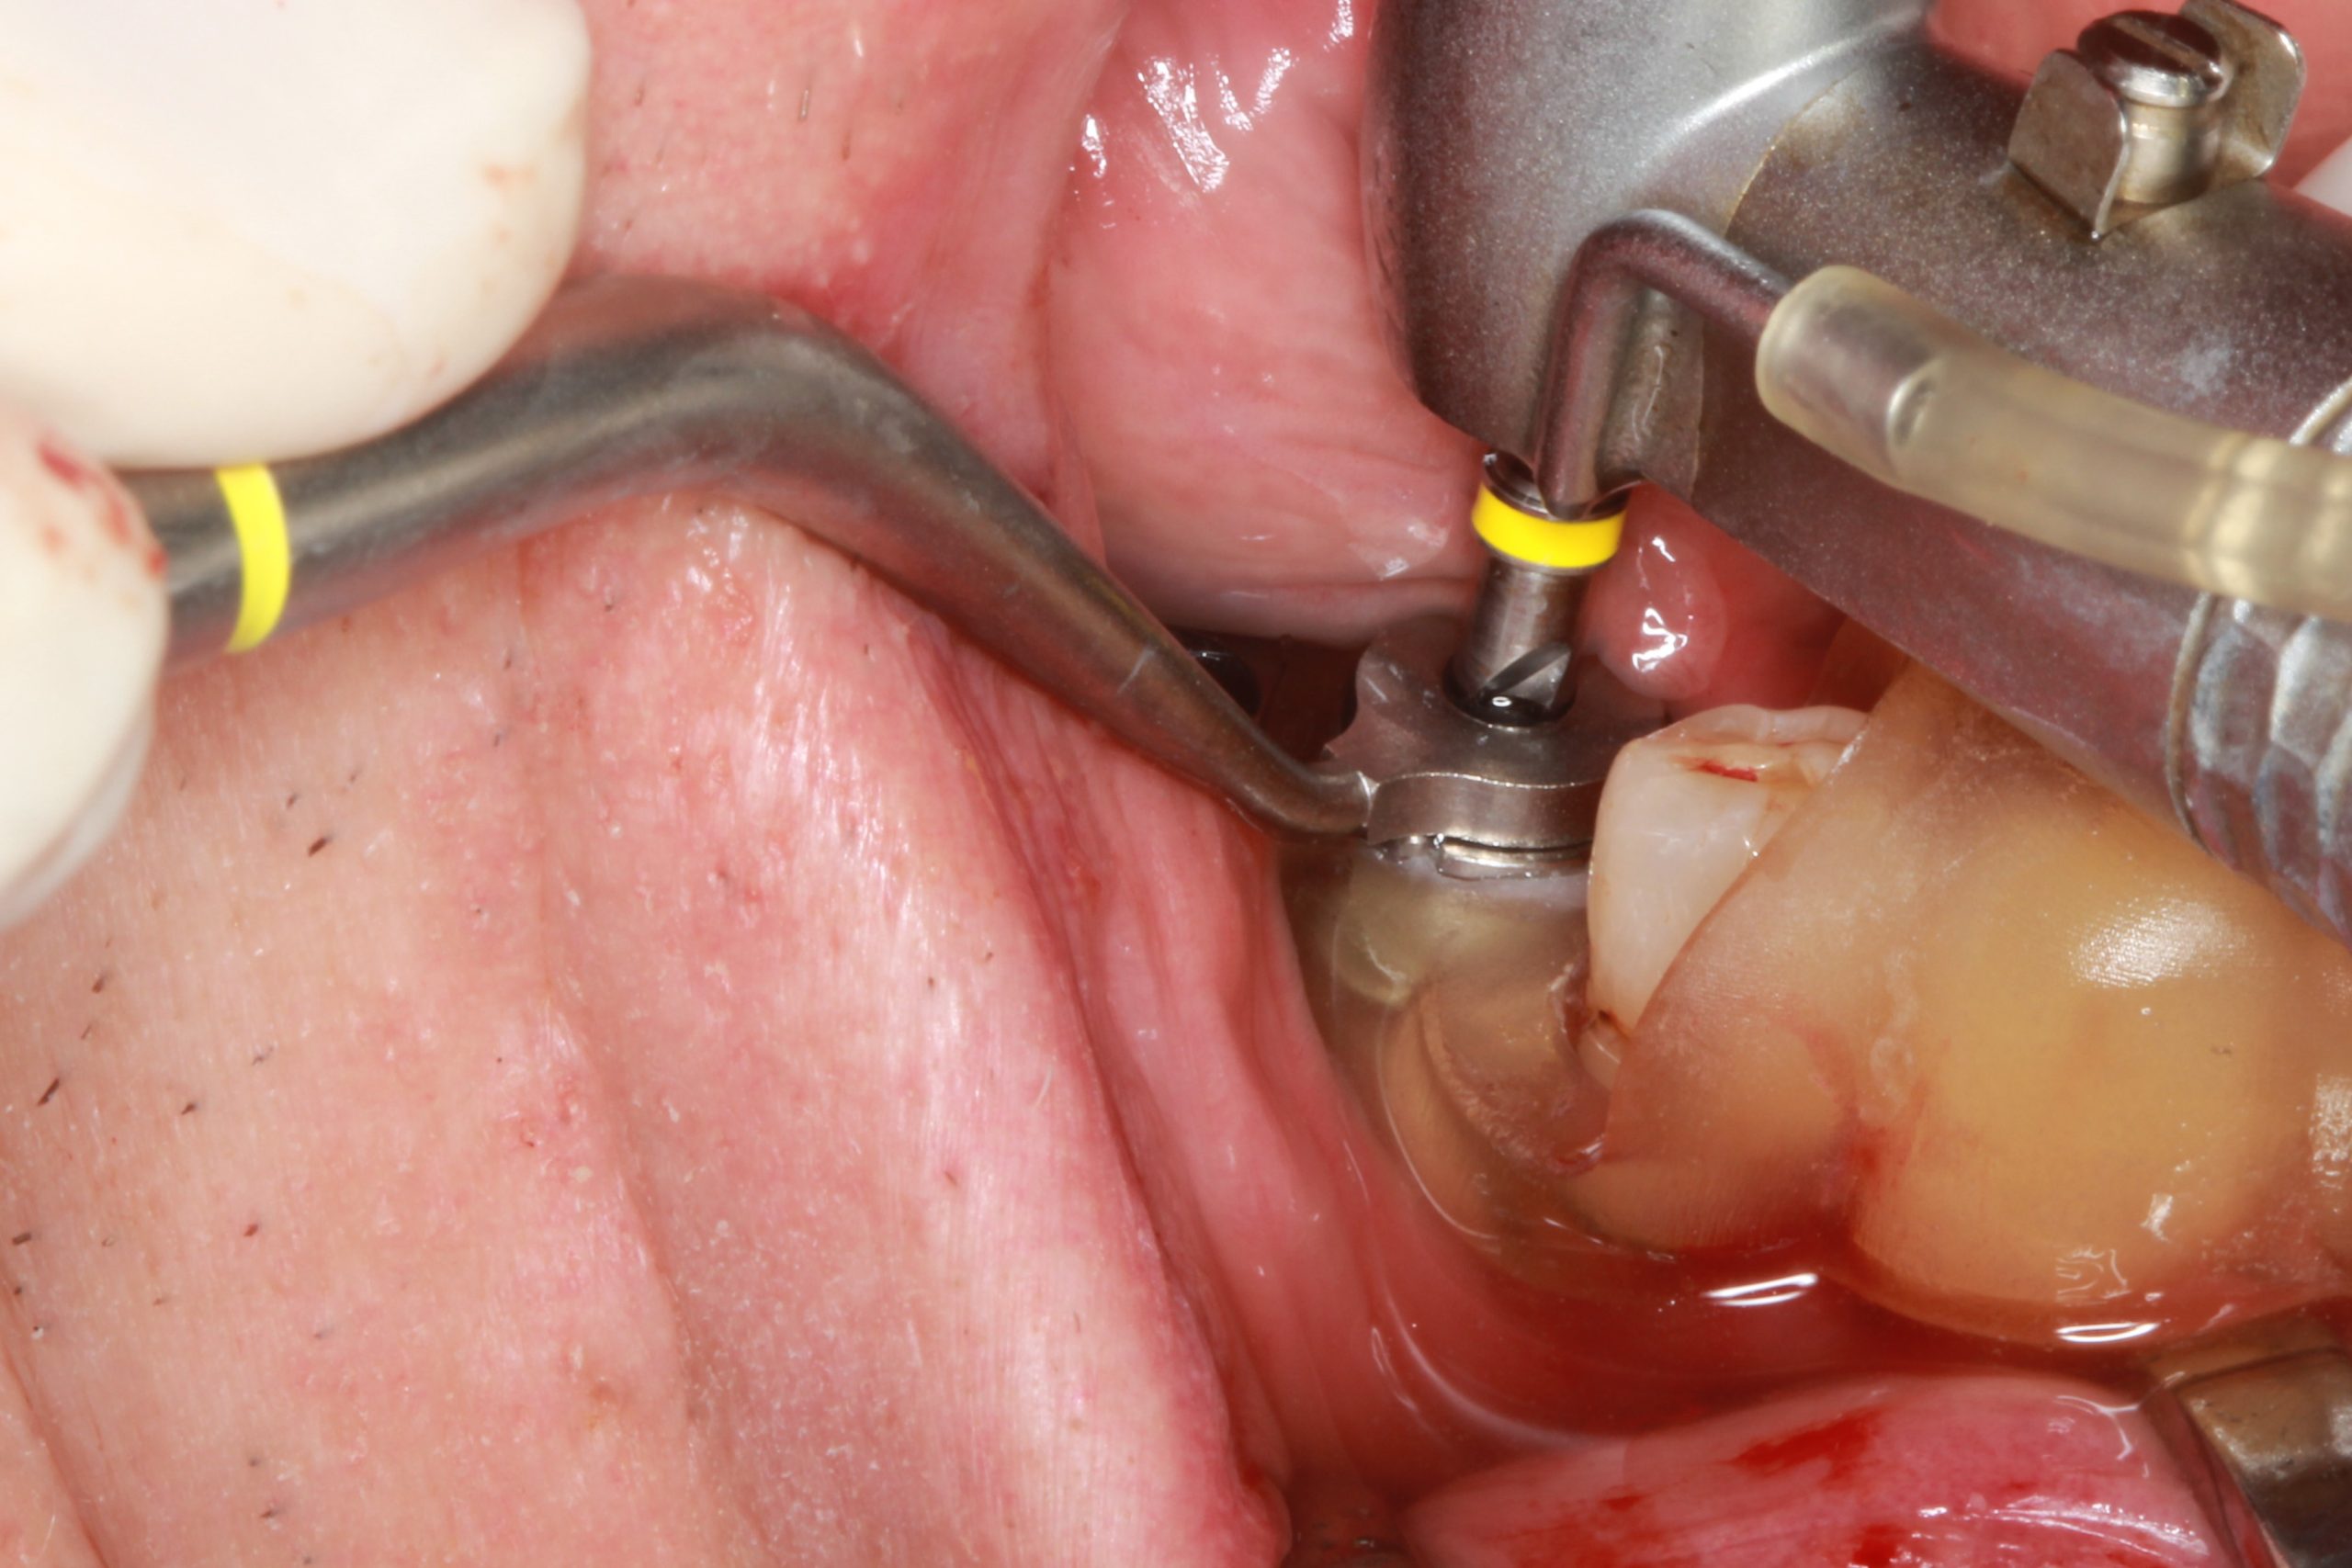

Gemäß dem Operationsprotokoll begann die Präparation mit dem Bohrer S2.9 für die schablonengeführte Chirurgie mit der erforderlichen Länge und mit dem Bohrlöffel S2.9 (mit gleichem Farbstreifen) des kleinsten Durchmessers von 2,3 mm.

Dann wurde die Behandlung mit den geführten Bohrern und den Bohrlöffeln für den entsprechenden Implantatdurchmesser fortgesetzt.

Die Präparation wurde mit Anwendung von geführten Versenkbohrern und Gewindeschneidern mit C-Löffeln abgeschlossen. Die Implantatinsertion wurde nach Entfernen der Chirurgieschablone durchgeführt.